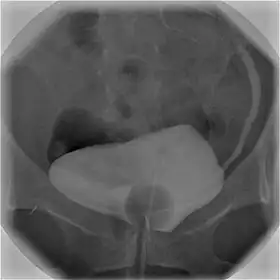

Cystography image showing contrast in the urinary bladder and left ureter (right side of image).

In radiology and urology, a cystography (also known as cystogram) is a procedure used to visualise the urinary bladder.

Using a urinary catheter, radiocontrast is instilled in the bladder, and X-ray imaging is performed. Cystography can be used to evaluate bladder cancer, vesicoureteral reflux, bladder polyps, and hydronephrosis. It requires less radiation than pelvic CT, although it is less sensitive and specific than MRI or CT. In adult cases, the patient is typically instructed to void three times, after which a post voiding image is obtained to see how much urine is left within the bladder (residual urine), which is useful to evaluate bladder contraction dysfunction. A final radiograph of the kidneys after the procedure is finished is performed to evaluate for occult vesicoureteral reflux that was not seen during the procedure itself.[1]